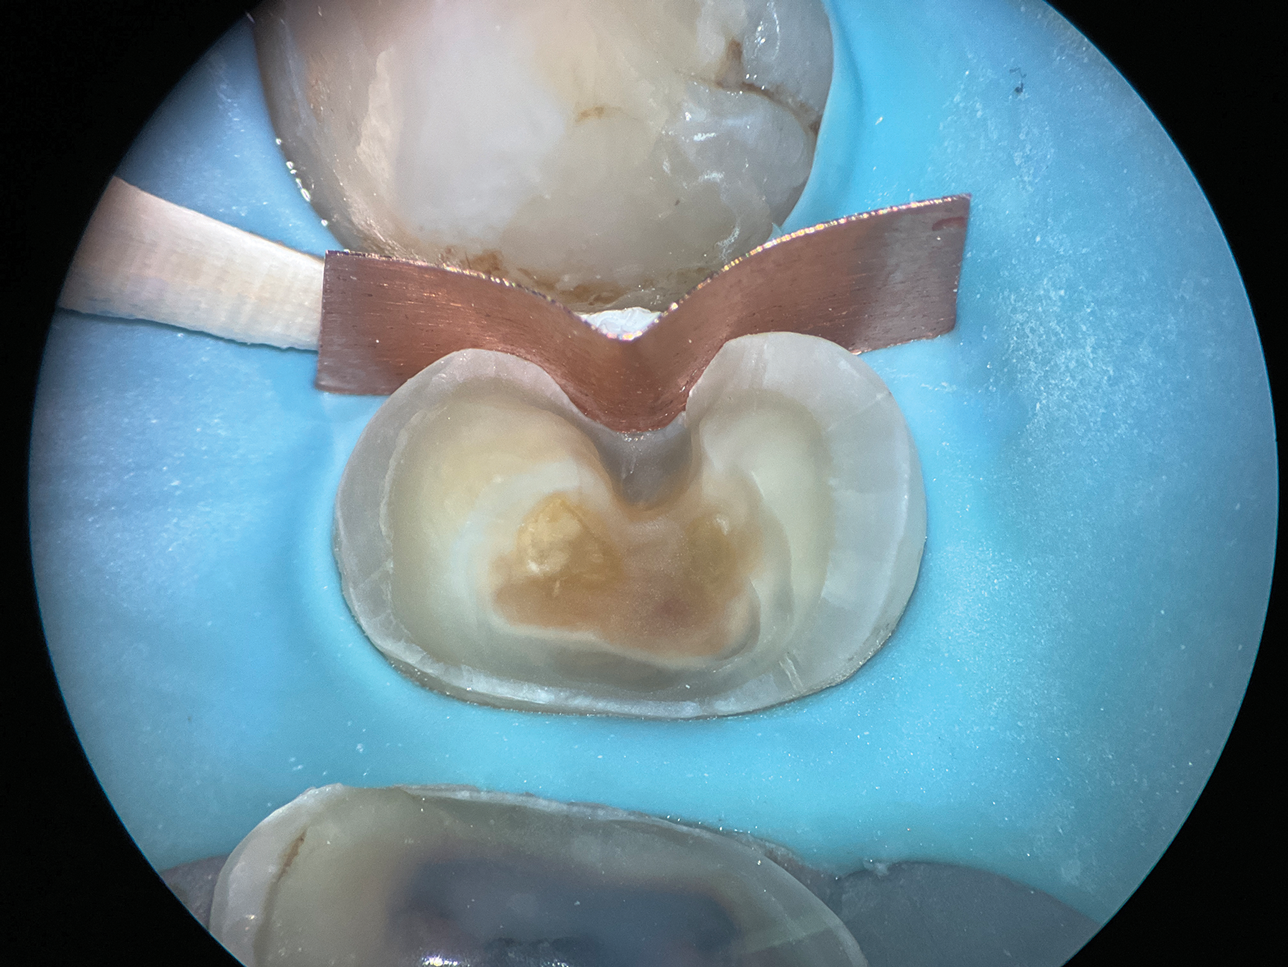

(8.) Close-up occlusal view of a maxillary first molar after the removal of deep subgingival caries, where despite rubber dam isolation, infiltration of blood and saliva into the cavity has occurred.

Figure 8

(9.) Close-up occlusal view of the maxillary first molar prepared for a matrix-in-matrix technique with a circumferential matrix supported by a 3-mil copper band inside for proper adaptation to the margin’s concave and convex areas. Note the addition of a liquid dam material placed between the two matrices for added stability.

Figure 9